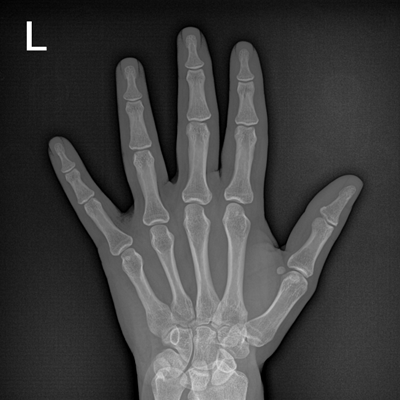

● 數(shù)字化無(wú)線平板成像,操作簡(jiǎn)便,成像質(zhì)量高